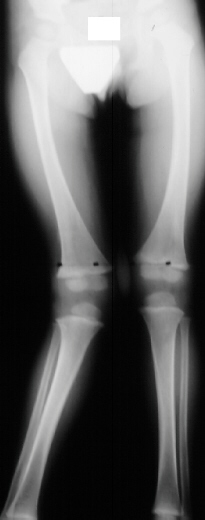

This 2 year and 9 month old male presented for evaluation of a worsening

valgus deformity of his right knee. Thirteen months ago, his mother states

the patient complained of some right leg pain and a limp, unassociated

with recognized trauma. The pain and limp resolved over a number of weeks.

Mom has noticed a progressive cosmetic deformity of the leg without any

complaints of pain or functional limitation in running or walking. At the

time of the initial injury, the patient was examined by his doctor but

there was no history of injury and the problem was not considered to be

significant; therefore, no x-rays were performed to document the possibility

of a fracture. On physical examination moderate to severe genu valgum of

25 degrees of the right knee and 5 degrees of genu valgum of the left knee

was noted. The right knee had full, painless range of motion without ligamentous

instability. The left iliac crest was higher than the right. There was

no significant rotational deformity noted at the hip, knee or ankle. On

gait examination, patient was able to walk and run without tripping or

displaying a functional deficit. Standing AP films of the bilateral lower

extremities revealed a tibial femoral angle of 17 degrees of the right

knee(image1). At a four month follow up now 13 months after injury a progression

to 27 degrees was noted(image2). Neutral alignment of the left knee was

noted.